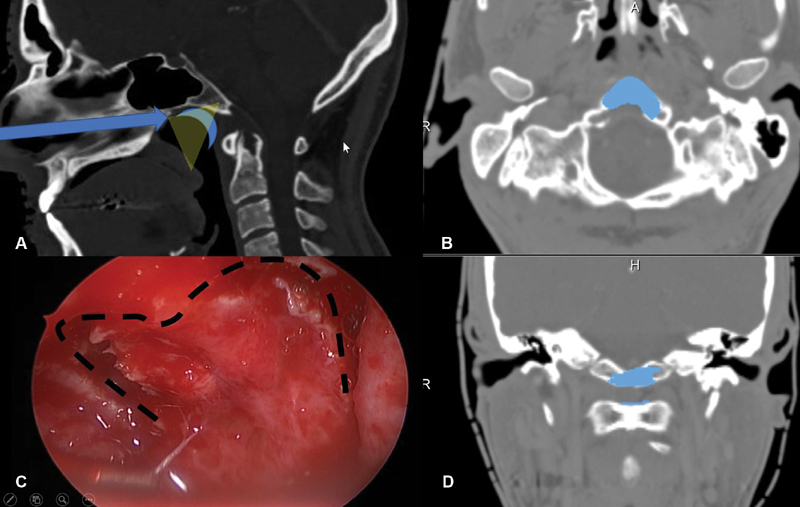

术中通过磁共振成像(MRI)监测术后神经功能缺损和术后肿瘤体积。在鼻内窥镜下以30度和45度角行双鼻孔入路。随后,制作一个心形皮瓣,钻取斜坡以暴露病变(图2)。在初始减压后,轻轻钻取C1环以到达齿状突内及周围的肿瘤,并进行完整切除。

图2:内镜鼻内入路手术技术示意图。(A)显示手术路径(蓝色箭头),以及在鼻咽上部(蓝月牙)形成的心形皮瓣的位置。这张图强调了需要有角度的内窥镜进行更好的术中视野暴露(黄色半透明三角形)(B)为轴向视图,(C)显示了为获得心形皮瓣而进行的切口的术中内窥镜视图,如本例中所用,(D)为冠状视图。(B和D)显示了术后图像分析的结果,在此过程中,Froelich教授对进行骨磨除的部位进行了分段(蓝色),并将其投影到患者的术前CT扫描上。注意,除了下斜坡外,C1环的上部分也被轻微钻孔以到达齿状突的肿瘤。